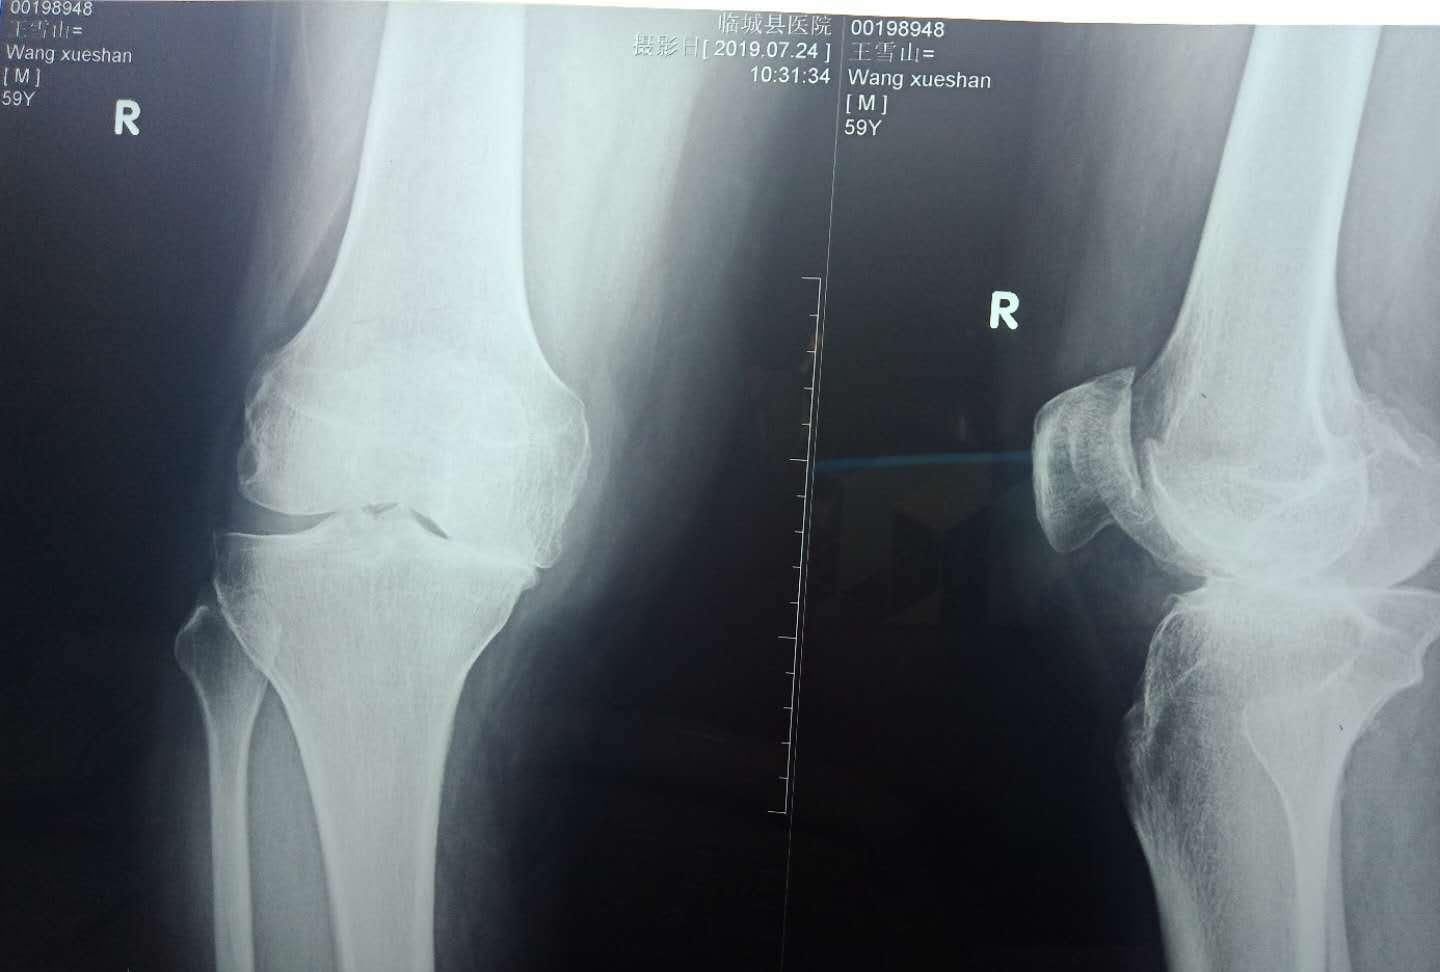

那么,什么是骨质增生呢?骨质增生是指关节软骨的改变,主要有椎骨边缘或关节边缘、关节面及骨实处骨小梁增多和骨密度增高或骨质疏松。因有时其增生形状像口唇或鸟嘴等,故称唇状突起或骨赞,一般人称之为骨刺。骨质增生实际上是生理病理学名称,不应视为一种疾病,分为原发性和继发性两种。原发性骨质增生是人体为适应应力的变化,维持关节内外平衡而产生的一种防御性反应,是生理代偿性改变,即生理学的老化现象,是人体在成年期后开始发生的老年性组织器宜退化变性的生理进程,如同人老了要起皱纹、长白发一样正常。任何人到40岁左右,在活动较多负重较大的膝、腰、颈等关节必然会出现程度不同的骨质增生。所以说骨质增生不是病,而是一种生理现象,是人体自卫、代偿、再生、修复和重建的正常功能,属于保护性生理反应。有了骨质增生,人体的关节才能更加稳定,骨质增生并不都需要治疗。骨质增生的实质是关节软骨退变和关节周围软组织拮抗力失衡的结果。只有当增生的骨质刺激压迫了血管、神经等软组织引起疼痛时,才能称为病,即骨质增生病,临床上这种机会是比较少的,也就是说真正引起症状的不是我们查出来的骨刺,比较多见的是骨刺引起的肌筋无菌性炎症造成的局部张力增高及静脉瘀阻。但在临床工作中,骨质增生显然被妖魔化了,我们且看下列现象。

现象一:患者骨质增生了,有的甚至关节变形了,有的甚至腰椎骨刺搭成骨桥了,症状很严重,疼痛酸账等。于是治疗开始:吃药、贴药、打针、输液等等,最后症状消失,可关节变形依然,再摄X光片,发现增生依旧。证明:疼痛麻木等症状与骨质增生无直接关系。

现象二:患者身强体健,但年事渐高,夜晚受凉或扭伤后去医院检查,摄X 光片显示骨质增生,医生遂按骨质增生制订治疗方案。呜呼!难道骨刺能一夜暴长,如玉米拔节吗?答:非也,骨质增生本存在,此乃肌肉、切带等软组织损伤所致。试想:多年来,多少老年人受到了“骨质增生”的不公正诊断。

现象三:年龄大了,尽管身体没有不适,为防患于未然,做个体检,结果吓人一跳,颈椎3、4、5骨质增生,腰椎1~5节骨质增生,膝关节骨质增生。查出一身病来,患者吓个半死,如何是好?可为什么不疼痛呢?答:骨质增生不是骨质增生病。